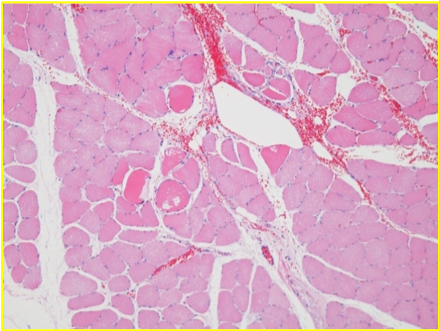

Necrosis

25 min post endopeel

desorganización observada 25 min después del endopeel

reorganization 60 min after endopeel

reorganización 60 min después de endopeel

después de 0,05 ml de inyección de endopeel

Departamento de Investigación de Órganos y Sistemas, Universidad de Akita, Facultad de Medicina y Clínicas YMC-Biyou Yokohama Minato y Shinjuku

ANALISIS:Instituto de Investigación Patológica de Sapporo Ltd.